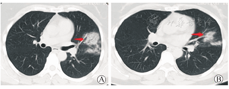

患者女,48岁,因"发热6 d"于2020年1月21日收治金华市中心医院感染科隔离病房。患者6 d前无明显诱因下出现发热,无规律性,体温最高为38.3℃,偶有心悸,能自行缓解,无其他不适,于1月21日就诊我院发热门诊,查体:体温37.3℃,脉搏93次/min,呼吸20次/min,血压143/97 mmHg(1 mmHg=0.133 kPa),神志清,精神可,口唇无发绀,咽部稍充血,扁桃体Ⅰ度肿大,双肺呼吸音粗,未及明显干湿啰音,心率93次/min,律齐,未及病理性杂音。血常规示白细胞6.69×109/L,嗜中性粒细胞占比0.543,淋巴细胞占比0.305,超敏C-反应蛋白(CRP)8.9 mg/L。胸部CT提示左肺上叶可见片状高密度影。影像诊断:左肺上叶感染考虑,建议治疗后复查(图1)。患者既往体健。1月14日与来自武汉伴有发热的同事有密切接触史,经医院专家组会诊,收治感染科隔离病房。

注:箭头标注为早期肺内病灶